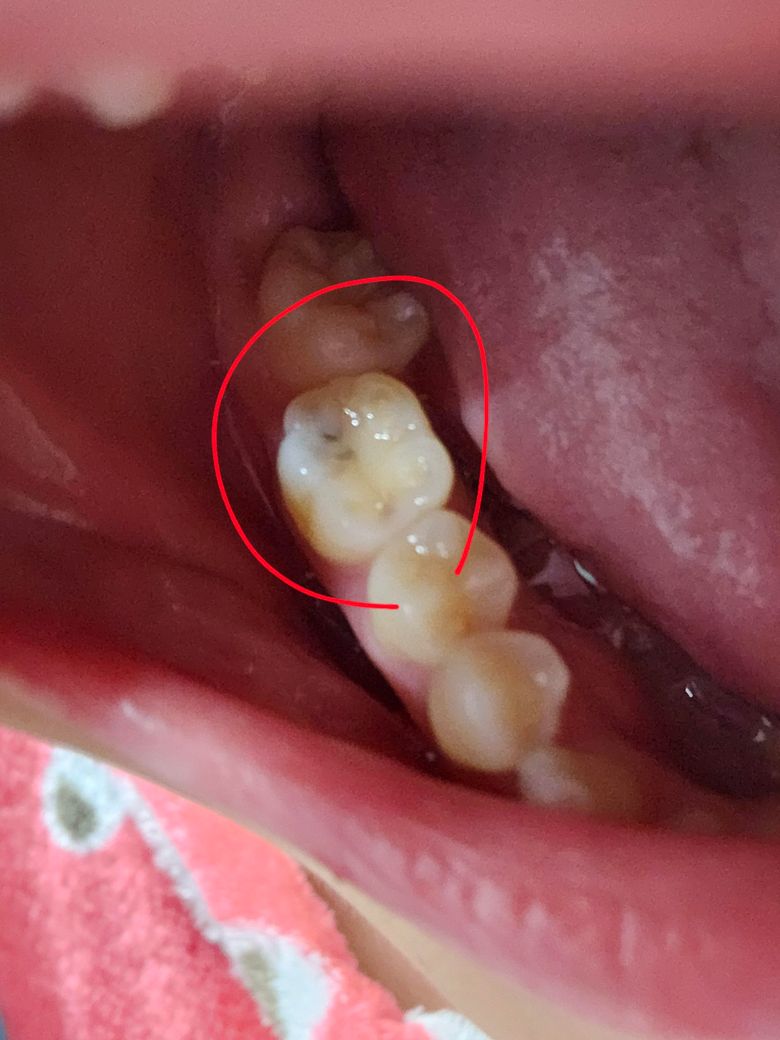

사진처럼 보이는 치아는 중지된 충치일 수 있나요?

이쑤시개로 쑤셔봤는데 아프지도 않고 긁히지도 않아요.. 진행중인 충치라면 어떤 치료를 받는게 제일 자연치아를 안건드릴수있나요?

• 1번 째 사진

충치가 치아 표면의 틈, 특히 치아 사이나 교합면의 작은 균열로 침투하여 내부에서 상아질을 침식할 수 있습니다. 사진에서 보이는 치아가 검게 변색되었다면, 그것이 이미 진행이 멈춘 중지된 충치이거나 진행초기일 가능성이 있습니다.

치아 내부 충치는 엑스레이나 정밀 검사를 통해 확인해야만 정확한 진단이 가능하기에 보다 정확한 상태 확인을 위해 치과 진료를 권합니다.